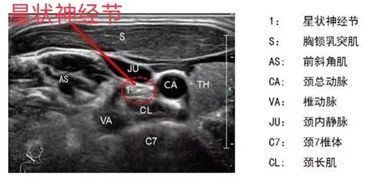

超聲引導(dǎo)下可清晰顯示星狀神經(jīng)節(jié)的位置及包繞星狀神經(jīng)節(jié)周圍的神經(jīng)、血管、氣管等危險(xiǎn)結(jié)構(gòu),引導(dǎo)穿刺針精確直達(dá)星狀神經(jīng)節(jié)周圍(穿刺針極細(xì),患者全程幾乎沒有痛感),創(chuàng)傷小、定位精確、安全性高、療效顯著,是一項(xiàng)高效、實(shí)用的微創(chuàng)技術(shù)。